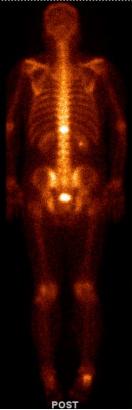

左:2017-01-25放疗后复查全身骨扫描;右:2017-07-15放疗后复查全身骨扫描

骨转移部位,病灶明显缩小,见下图,转移灶明显缩小

2018-04-19放疗后复查全身骨扫描